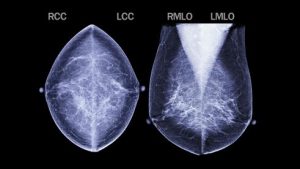

ম্যামোগ্রাফি হলো স্তনের বিশেষ ধরনের এক্স–রে। এই পরীক্ষায় খুব সামান্যই তেজস্ক্রিয় রশ্মি ব্যবহৃত হয়। ৫০ বছরের বেশি বয়সী নারীদের নিয়মিত স্তনের ম্যামোগ্রাফি করালে লাভই বেশি বলে বিভিন্ন গবেষণায় প্রমাণিত। তাই আন্তর্জাতিকভাবে ম্যামোগ্রাফি স্তন ক্যানসার স্ক্রিনিংয়ের একটি শক্তিশালী মাধ্যম হিসেবে বিবেচিত।

প্রথমে ম্যামোগ্রাফি যন্ত্রের দুই প্লেটের মধ্যে স্তন রাখা হয়। আস্তে আস্তে প্লেট দুটির মাধ্যমে স্তনের ওপর চাপ দেওয়া হয়। এরপর মেশিনের সুইচ টিপে ম্যামোগ্রাফি করা হয়। এই এক্স–রের সময় সামান্য ব্যথা বা অস্বস্তিবোধ হতে পারে। স্তনের কোনো অস্বাভাবিক পরিবর্তন কিংবা স্তনে চাকা বা পিণ্ড হলে, ক্যালসিফিকেশন বা ক্যালসিয়াম ধাতু জমা হলে এ পরীক্ষার মাধ্যমে তা বোঝা যায়। চাকা, মিহি ক্যালসিয়াম দানার উপস্থিতি, বিন্যাসের ধরন এবং অন্যান্য অনেক বিষয় বিবেচনায় নিয়ে ক্যানসার সন্দেহ করা হয়। আগে কখনো ম্যামোগ্রাফি করা থাকলে তা নতুন ম্যামোগ্রাফির সঙ্গে তুলনা করা গুরুত্বপূর্ণ।